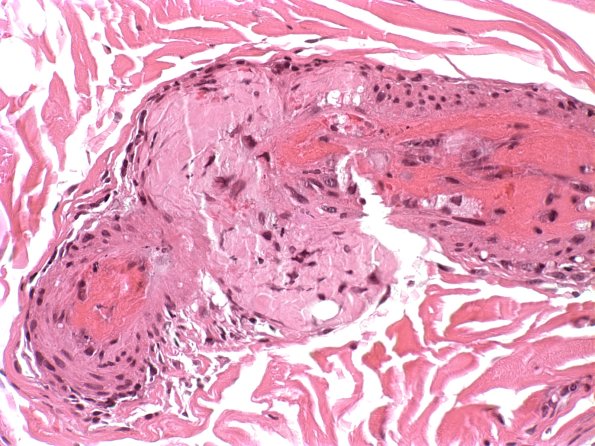

Washington University Experience | PERIPHERAL NEUROPATHY | 14 AMYLOID NEUROPATHY | 22A2 Amyloid neuropathy (Case 22) H&E 2

22A2,3 Deeper sections show the association of the amyloid shown in image #22A1 with fibrinoid vascular necrosis. (H&E)